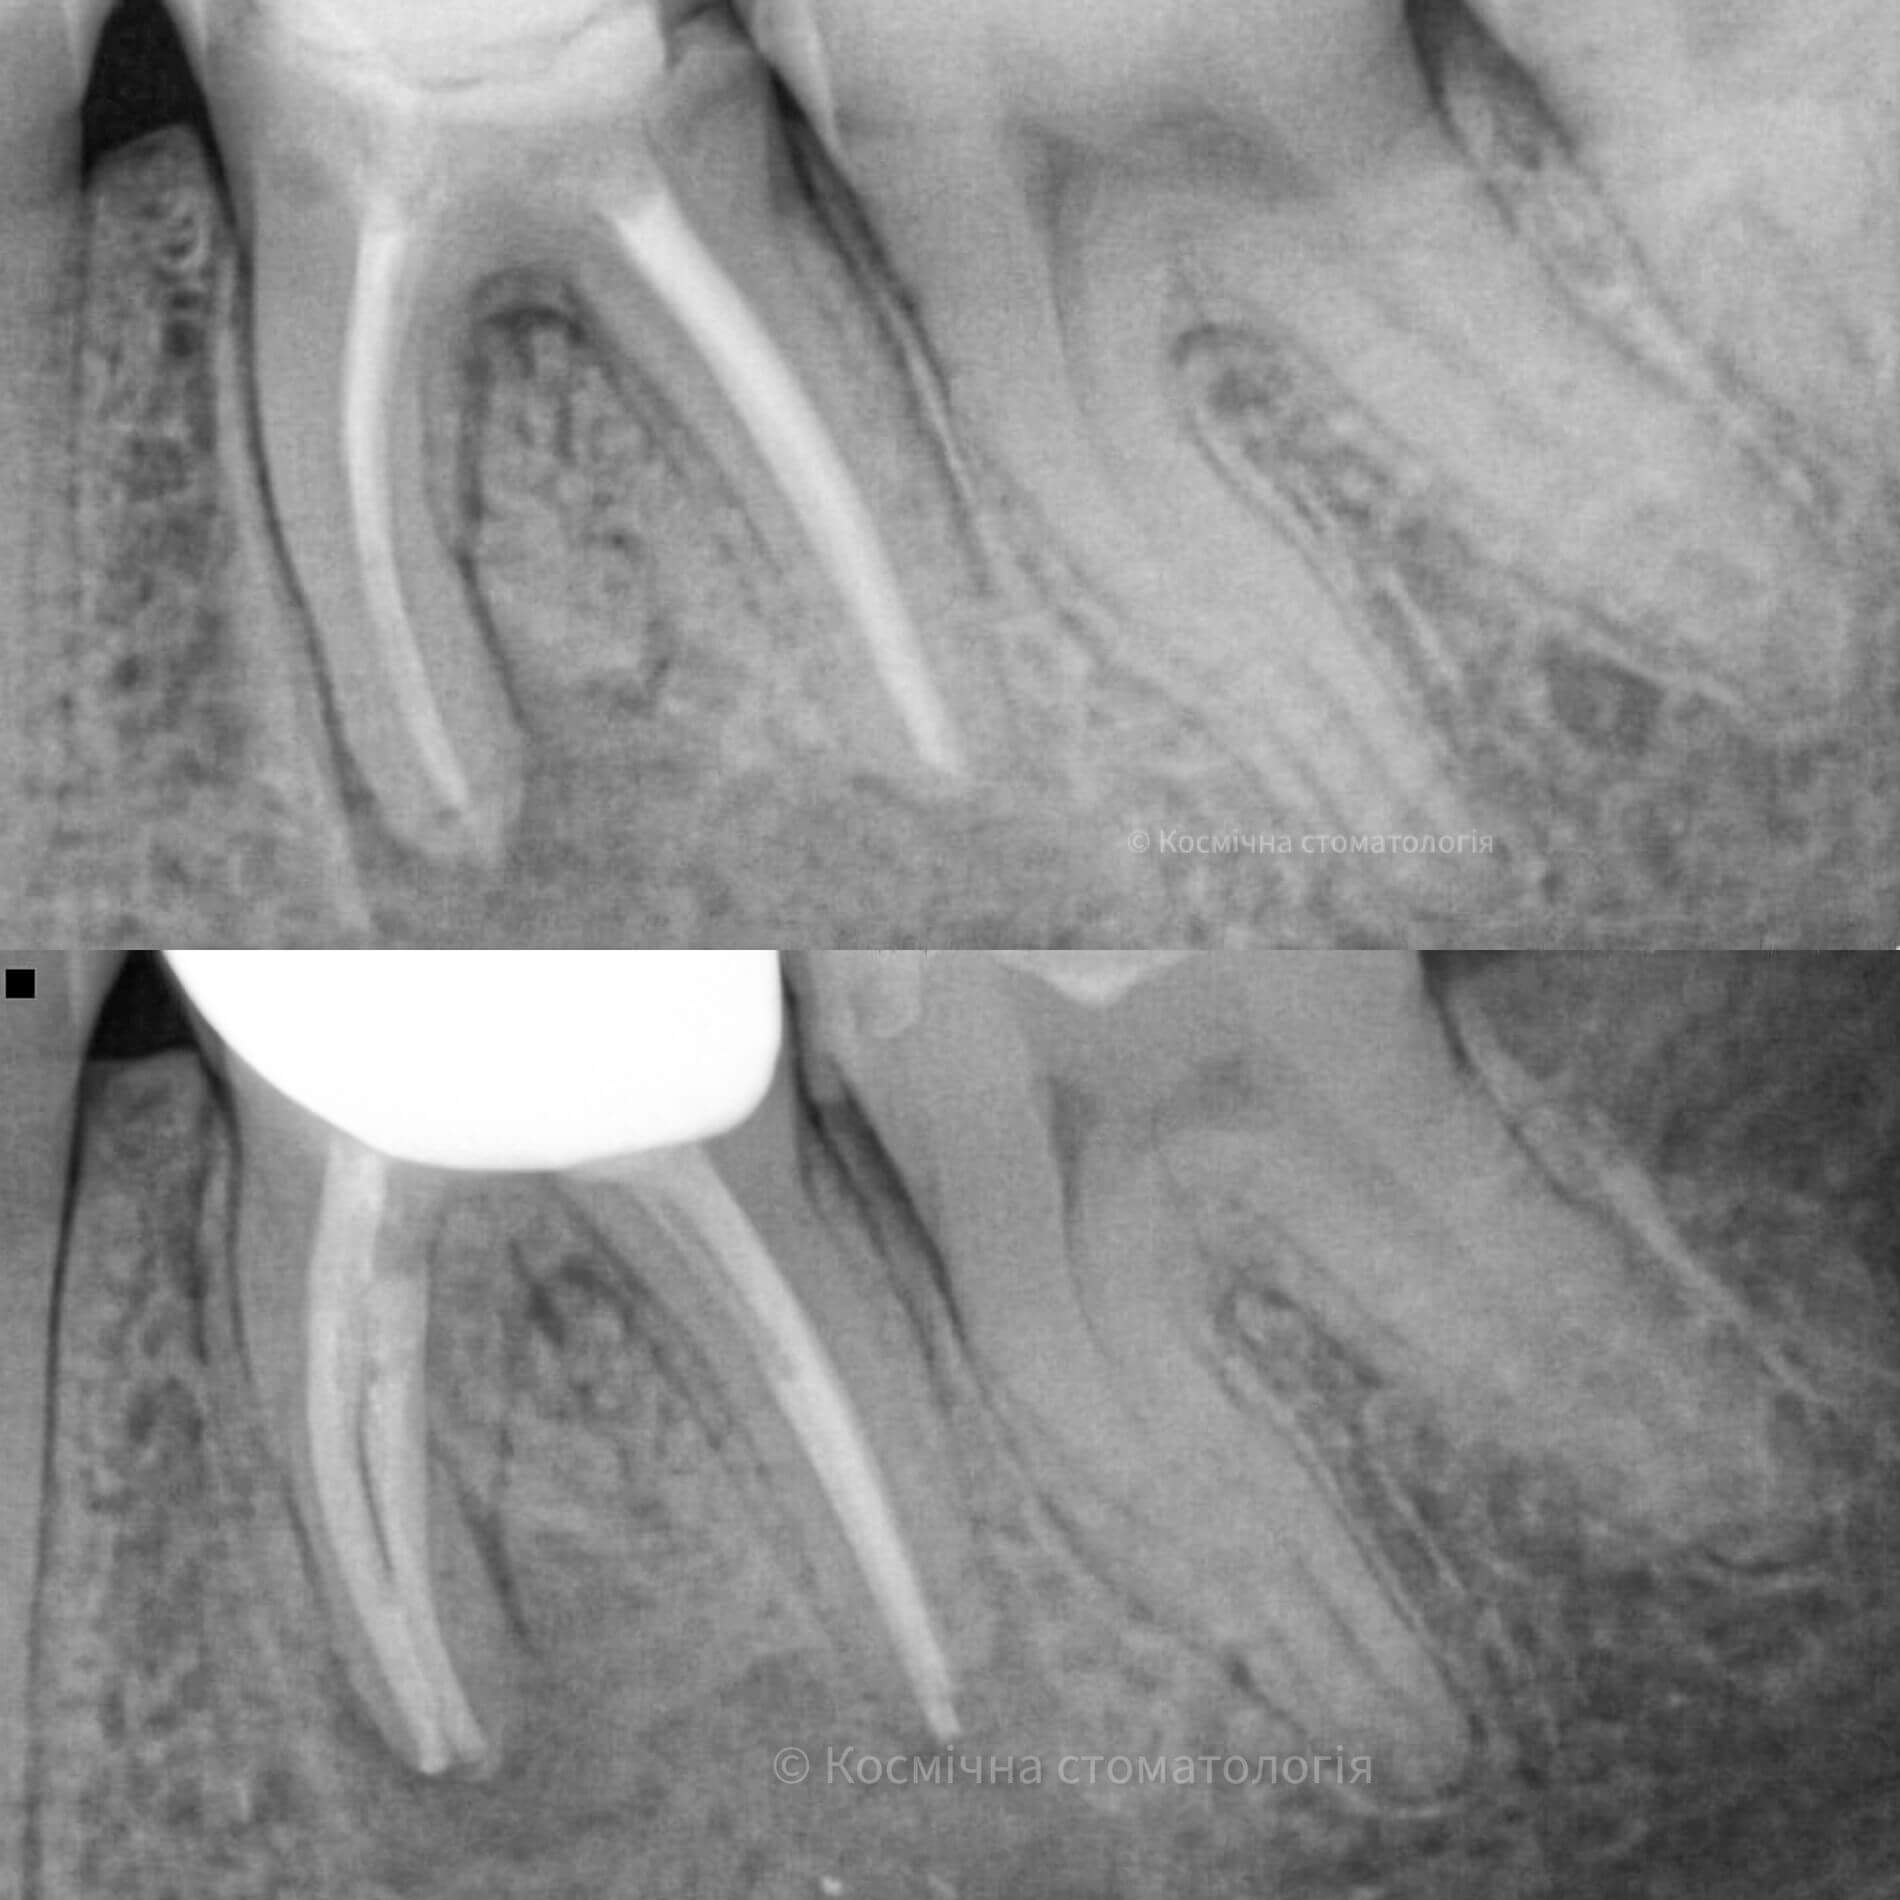

Мы уже говорили, качественное лечение зубных каналов – это довольно сложный и трудоемкий процесс, но с ним с легкостью справится наша космическая команда. Эта процедура затруднена отсутствием полноценного доступа к операционной полости, да еще зубные каналы часто искривлены и очень узкие, что делает невозможным визуальный контроль за проведением процедуры.

Но инновационные технологии и применение рентгенологического контроля выводят лечение каналов зуба во Львове специалистами Космической стоматологии Драганчука на новый межгалактический уровень.

Чтобы провести процедуру лечения и пломбирования каналов, мы в космической стоматологии Драганчука используем оптическое увеличение с помощью микроскопа Carl Zeisse.

Он позволяет вывести изображение на большой экран и масштабировать его, чтобы наша космическая команда могла осуществить все необходимые манипуляции особенно скрупулезно. Благодаря такому оптическому контролю каждого этапа лечения, мы можем оценить его эффективность и предотвратить возникновение осложнений.